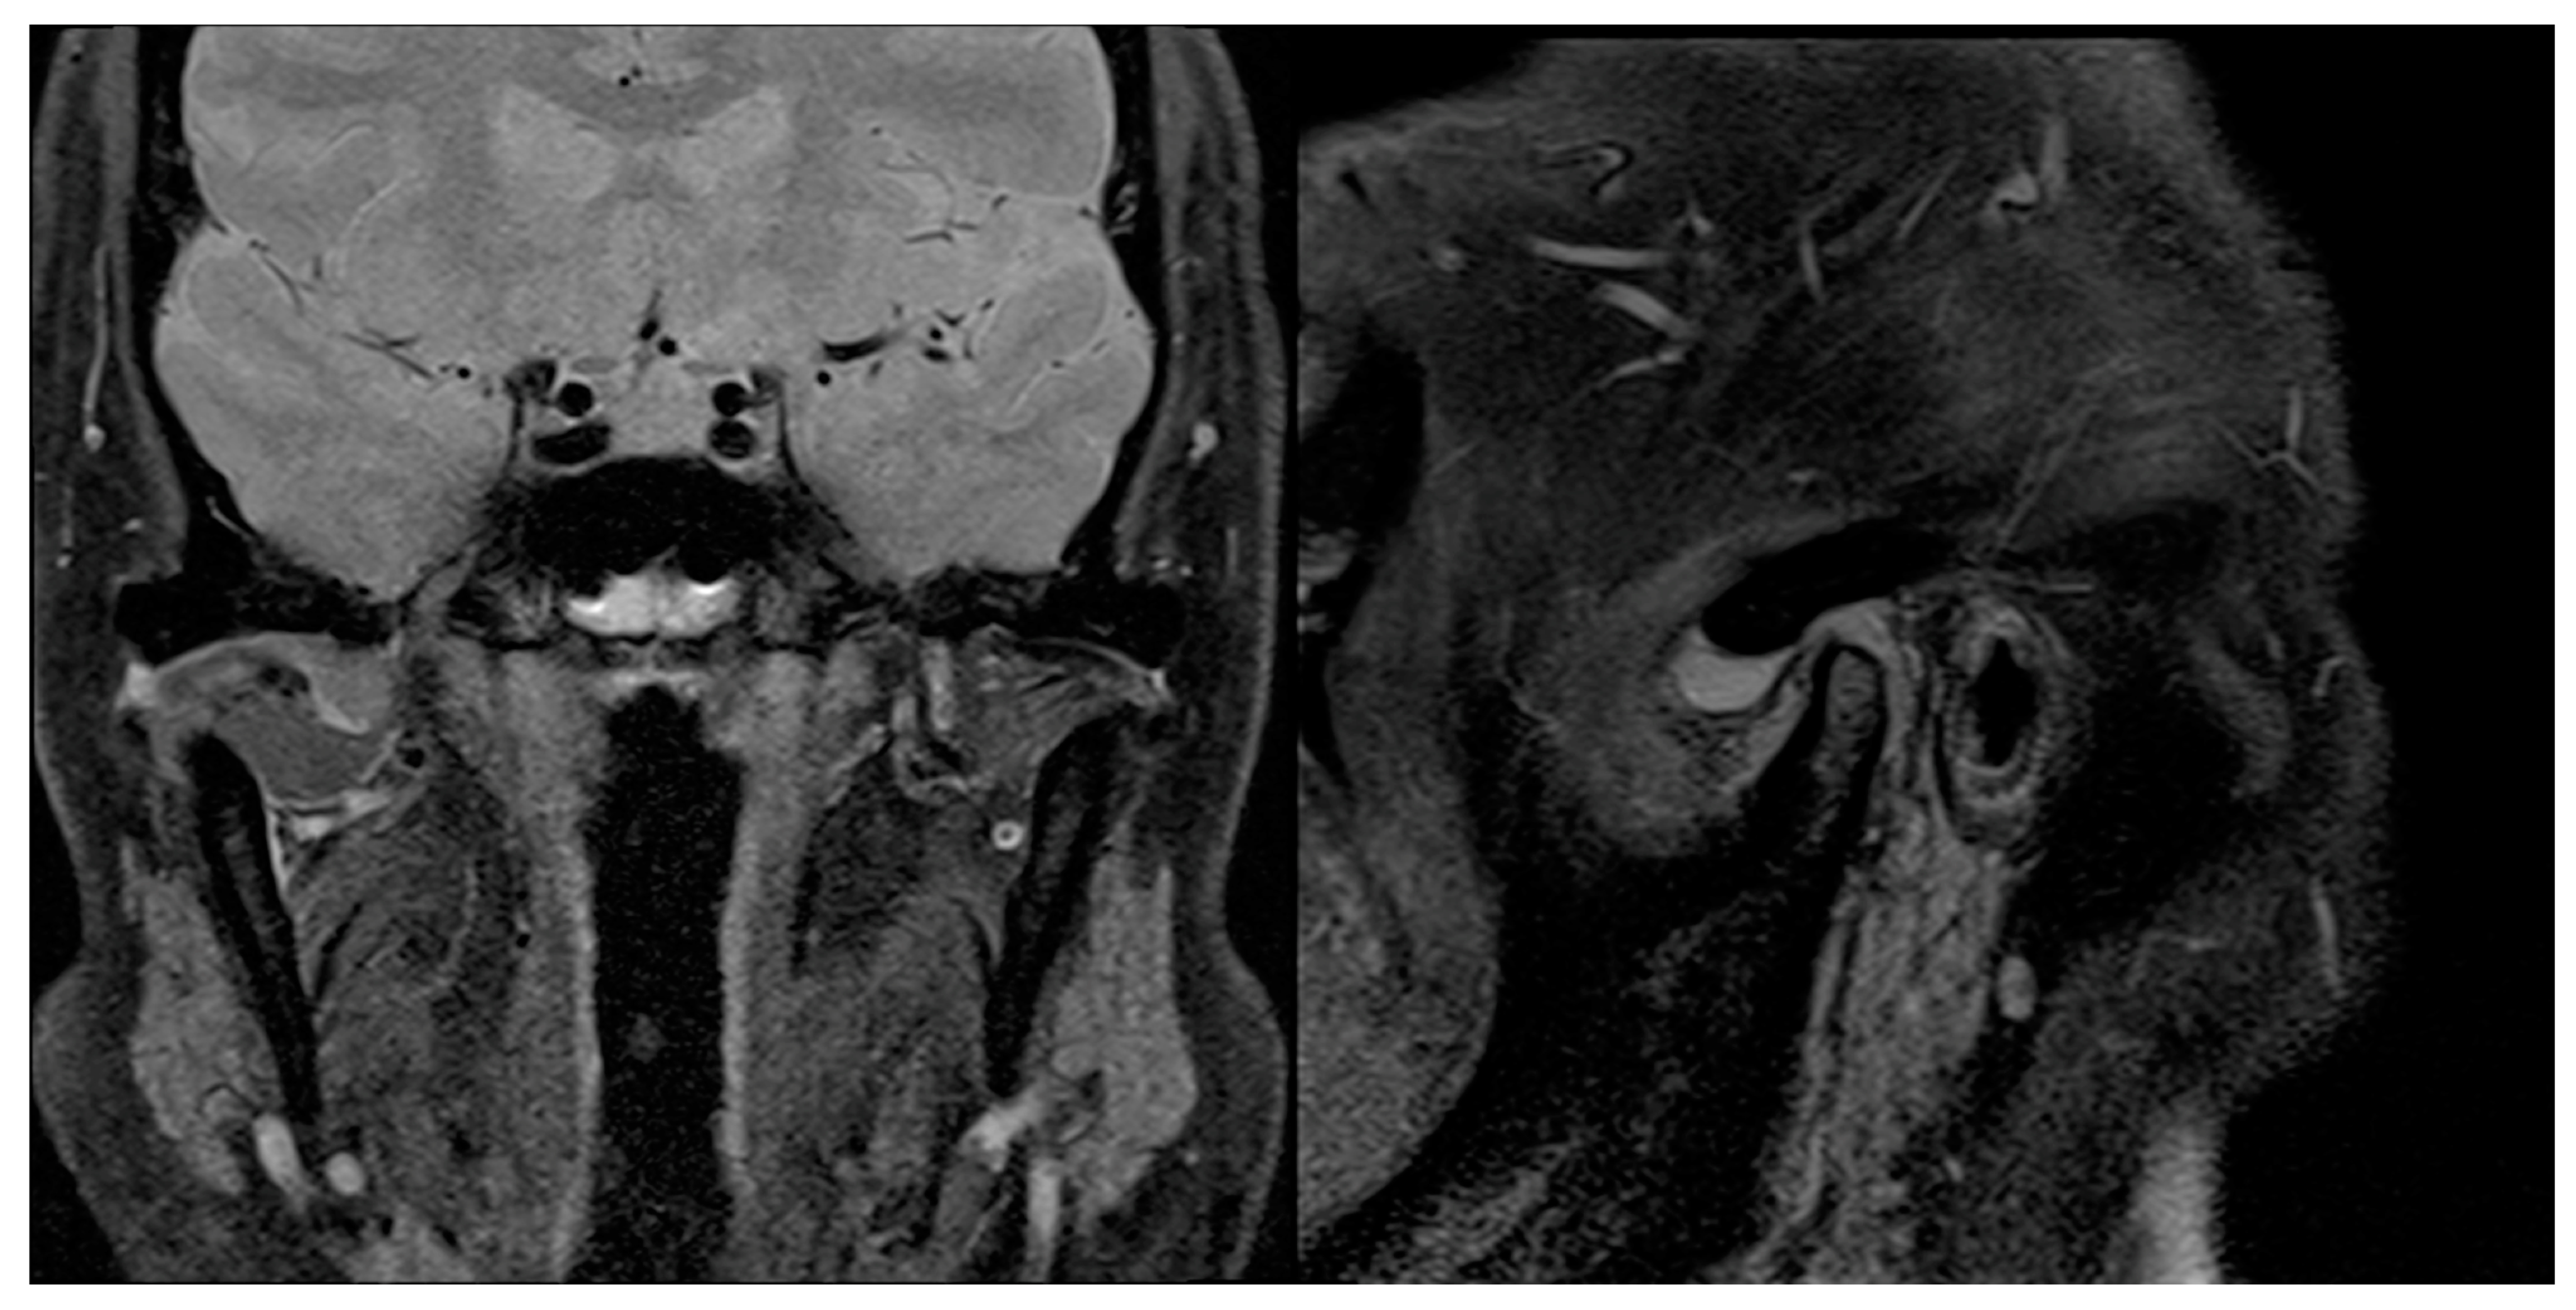

Figure 9.

Preoperative sagittal and coronal MRI scans showing, on the right, TMJ joint effusion and LBs, but no bony involvement.